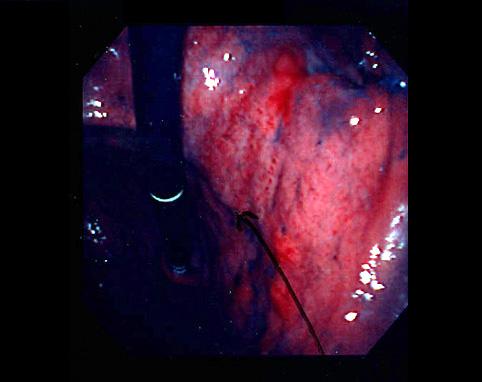

疾患(病理主体)の分類悪性上皮性腫瘍/腺癌

部位(臓器別)胃(部位)/前庭

検査方法内視鏡

腫瘍の肉眼分類3型(潰瘍浸潤型)/

病変の最大径(ミリ)40以上

腫瘍の深達度s(a)